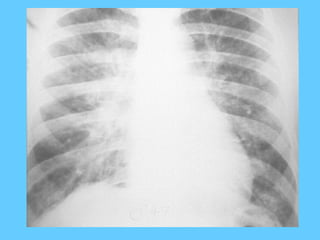

Cystic fibrosis

PA chest radiograph (a) and HRCT scan (b) in a 25-year-old patient with

cystic fibrosis. Chest radiograph shows diffuse overinflation and

cicatrization atelectasis of the right upper lobe. Tubular shadows

underlying dilated bronchi are present in the right lung bases and left

lung. HRCT scan shows decreased lung attenuation and mosaic

perfusion representing lesions of constrictive bronchiolitis. Mucoid

impactions within dilated bronchi are present within the collapsed right

upper lobe and the superior segment of the right lower lobe.